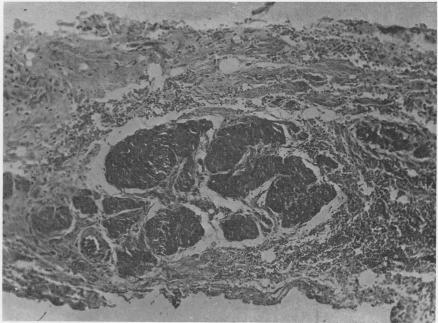

Congenital cysts of the mesentery; report of four cases.

Ann Surg. 1957 Mar;145(3):428-36. doi: 10.1097/00000658-195703000-00020.